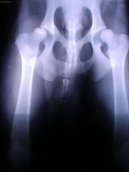

Obr.2: Artrotické změny na kyčelních kloubech 6 letého německého ovčáka s dysplazií. Tyto změny se vyvíjí postupně a až ve vyšším věku pacienta.

Dysplazie kyčelního kloubu je velmi častou vrozenou vadou u velkých a středních plemen. U většiny z nich se provádí povinné RTG vyšetření před uvedením do chovu.